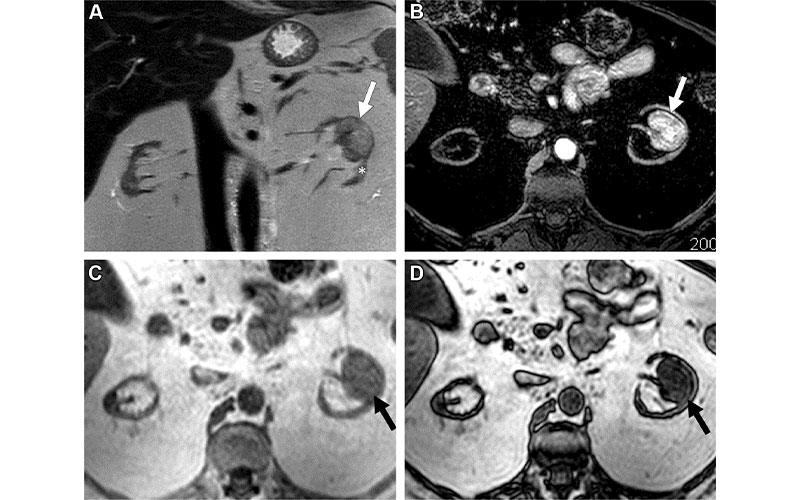

MRI scans in a 56-year-old woman with an indeterminate 3.2-cm left renal mass (arrow). (A) Coronal T2-weighted single-shot fast spin-echo image shows a left renal mass with heterogeneous signal intensity greater than that of the adjacent renal cortex (*). Note severe atrophy of both kidneys due to end-stage renal disease. (B) Axial fat-saturated T1-weighted spoiled gradient-echo image acquired during the corticomedullary phase after gadobenate dimeglumine administration (0.1 mmol per kilogram of body weight) shows intense heterogeneous enhancement that is higher than that of the adjacent renal cortex. Quantitative analysis demonstrated more than 75% enhancement in the renal mass compared with the renal cortex. (C, D) Axial T1-weighted gradient-echo in-phase (C) and opposed-phase (D) images show unequivocal presence of microscopic fat in the mass, with an apparent decrease in signal intensity in D compared with C. Both reviewers assigned a clear cell likelihood score of 5 in this mass. After nephrectomy, a diagnosis of clear cell renal cell carcinoma was confirmed.

Schieda et al, Radiology 2022; 303:590–599 ©RSNA 2022